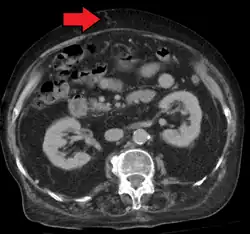

Portal hypertension due to cirrhosis resulting in revascularization of the umbilical vein

In addition, a widened (dilated) portal vein as seen on a CT scan or MRI may raise the suspicion about portal hypertension. A cutoff value of 13 mm is widely used in this regard, but the diameter is often larger than this is in normal individuals as well.[9]

A dilated portal vein (diameter of greater than 13 or 15 mm) is a sign of portal hypertension, with a sensitivity estimated at 12.5% or 40%.[18] On Doppler ultrasonography, a slow velocity of <16 cm/s in addition to dilatation in the main portal vein are diagnostic of portal hypertension.[19] Other signs of portal hypertension on ultrasound include a portal flow mean velocity of less than 12 cm/s, porto–systemic collateral veins (patent paraumbilical vein, spleno–renal collaterals and dilated left and short gastric veins), splenomegaly and signs of cirrhosis (including nodularity of the liver surface).[17]